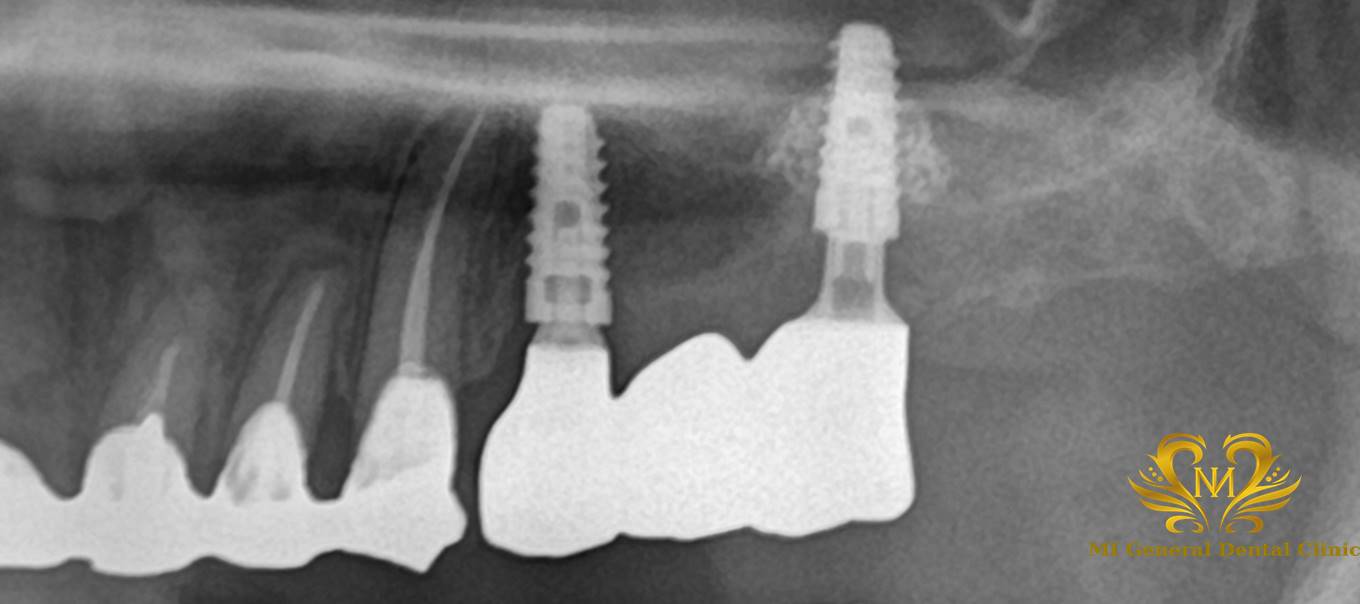

左上奥歯のインプラント治療

治療後

骨をたす骨造成という処置を行い、インプラント治療を行いました。

セラミックスの被せ物をすることにより、咬合の回復と見た目が美しくなりました。

| 治療内容 | 骨造成後にインプラント体の埋入を行い、インプラント体に負荷をかける仮歯にかえて、調整を行い、セラミックスの被せ物の型取りを行い、完成です。 |